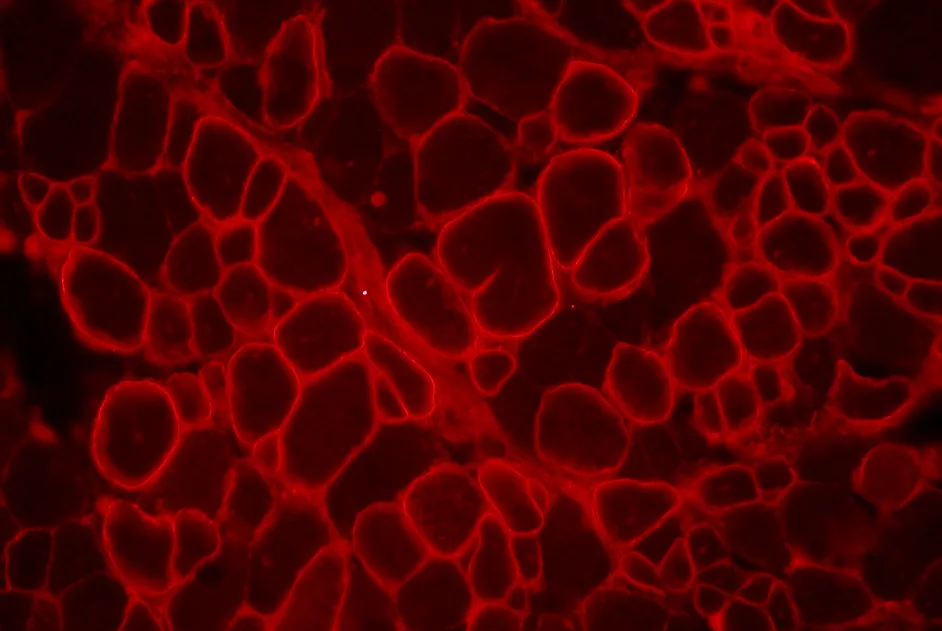

Mise en évidence d’un déséquilibre spécifique du stress oxydatif et d'un dysfonctionnement des mitochondries dans la dystrophie musculaire facio-scapulo-humérale